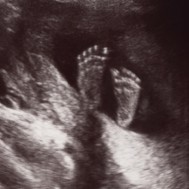

As the brain and nerve endings continue to develop, you may experiment with your sense of touch.[2] In this photo the baby is touching her ear.